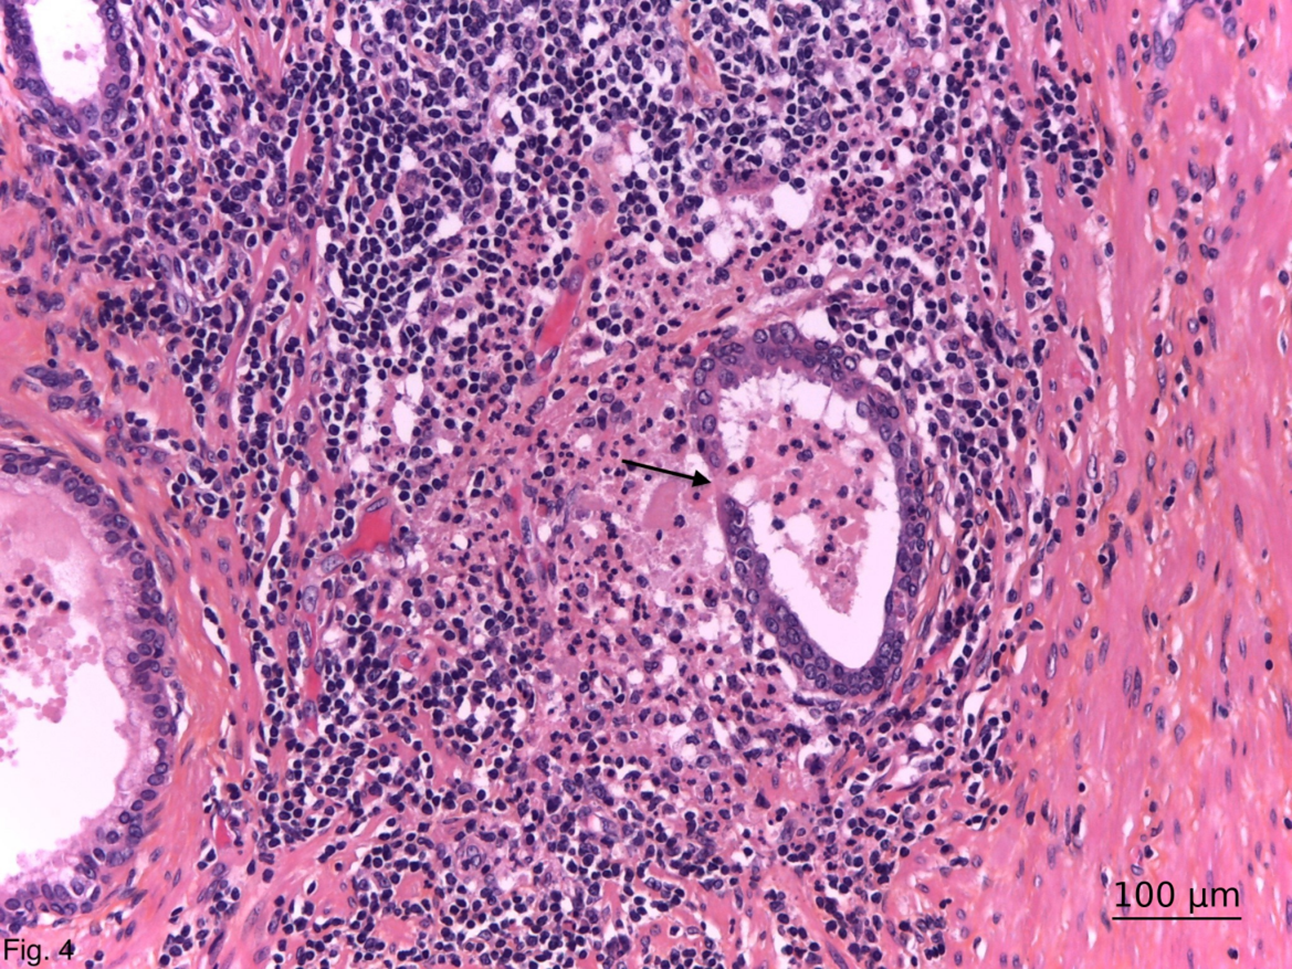

Our previous study describes that BLELs in the prostate are characterized by ductal epithelial distortion with intraepithelial lymphocytosis.6,7 Our observations demonstrate that, similar to glandular epithelium in other organs such as the pancreas, salivary glands, thyroid, and breast,23–26 the prostatic ductal epithelium can undergo transformation into specialized lymphoepithelium. The epithelium, overlying the ductal-associated lymphoid tissue in BLELs, changes its functional morphology and immunohistochemical profile in order to become specialized for the transport of antigens directly from the ductal lumen. Furthermore, we observed a strong membranous PD-L1 expression in these BLELs in cases of HG-HP. PD-L1 expression was found exclusively in inflamed prostatic tissue, particularly within the eosinophilic epithelial cells of BLELs, and was absent in normal or non-inflamed prostates.7 Its expression correlated with CI severity and mirrors immune checkpoint activity seen in autoimmune diseases like Sjögren’s syndrome and inflammatory bowel disease.22,25,26 We assume that the specialized PD-L1 positive BLEL plays a critical role as a gateway to the prostatic parenchyma. It has been shown to serve as an entry portal for antigens, like small intestinal and nasopharyngeal lymphoid tissues.27–29 It is obvious that BLEL are basic patho- and morphogenetic elements of HG-HP, reflecting morphologically the moment of epithelial barrier disruption (Figure 4). Obviously, this is followed by an influx of luminal antigenic substances that interact with the immune periductal cells (autoimmunisation), leading to dysbiosis of the prostate microbiome and an increased susceptibility to infection.3 The latter, once started, could establish a feed-forward mechanism resulting in a chronic, persistent HG inflammatory state (HG-HP).3

FIGURE 4. General view of high-grade histologic prostatitis with rupture of a ductal benign lymphoepithelial lesion (arrow) and diffusion of the intralumenal substances among immune periductal cells. Haematoxylin-eosin-safran; ×200